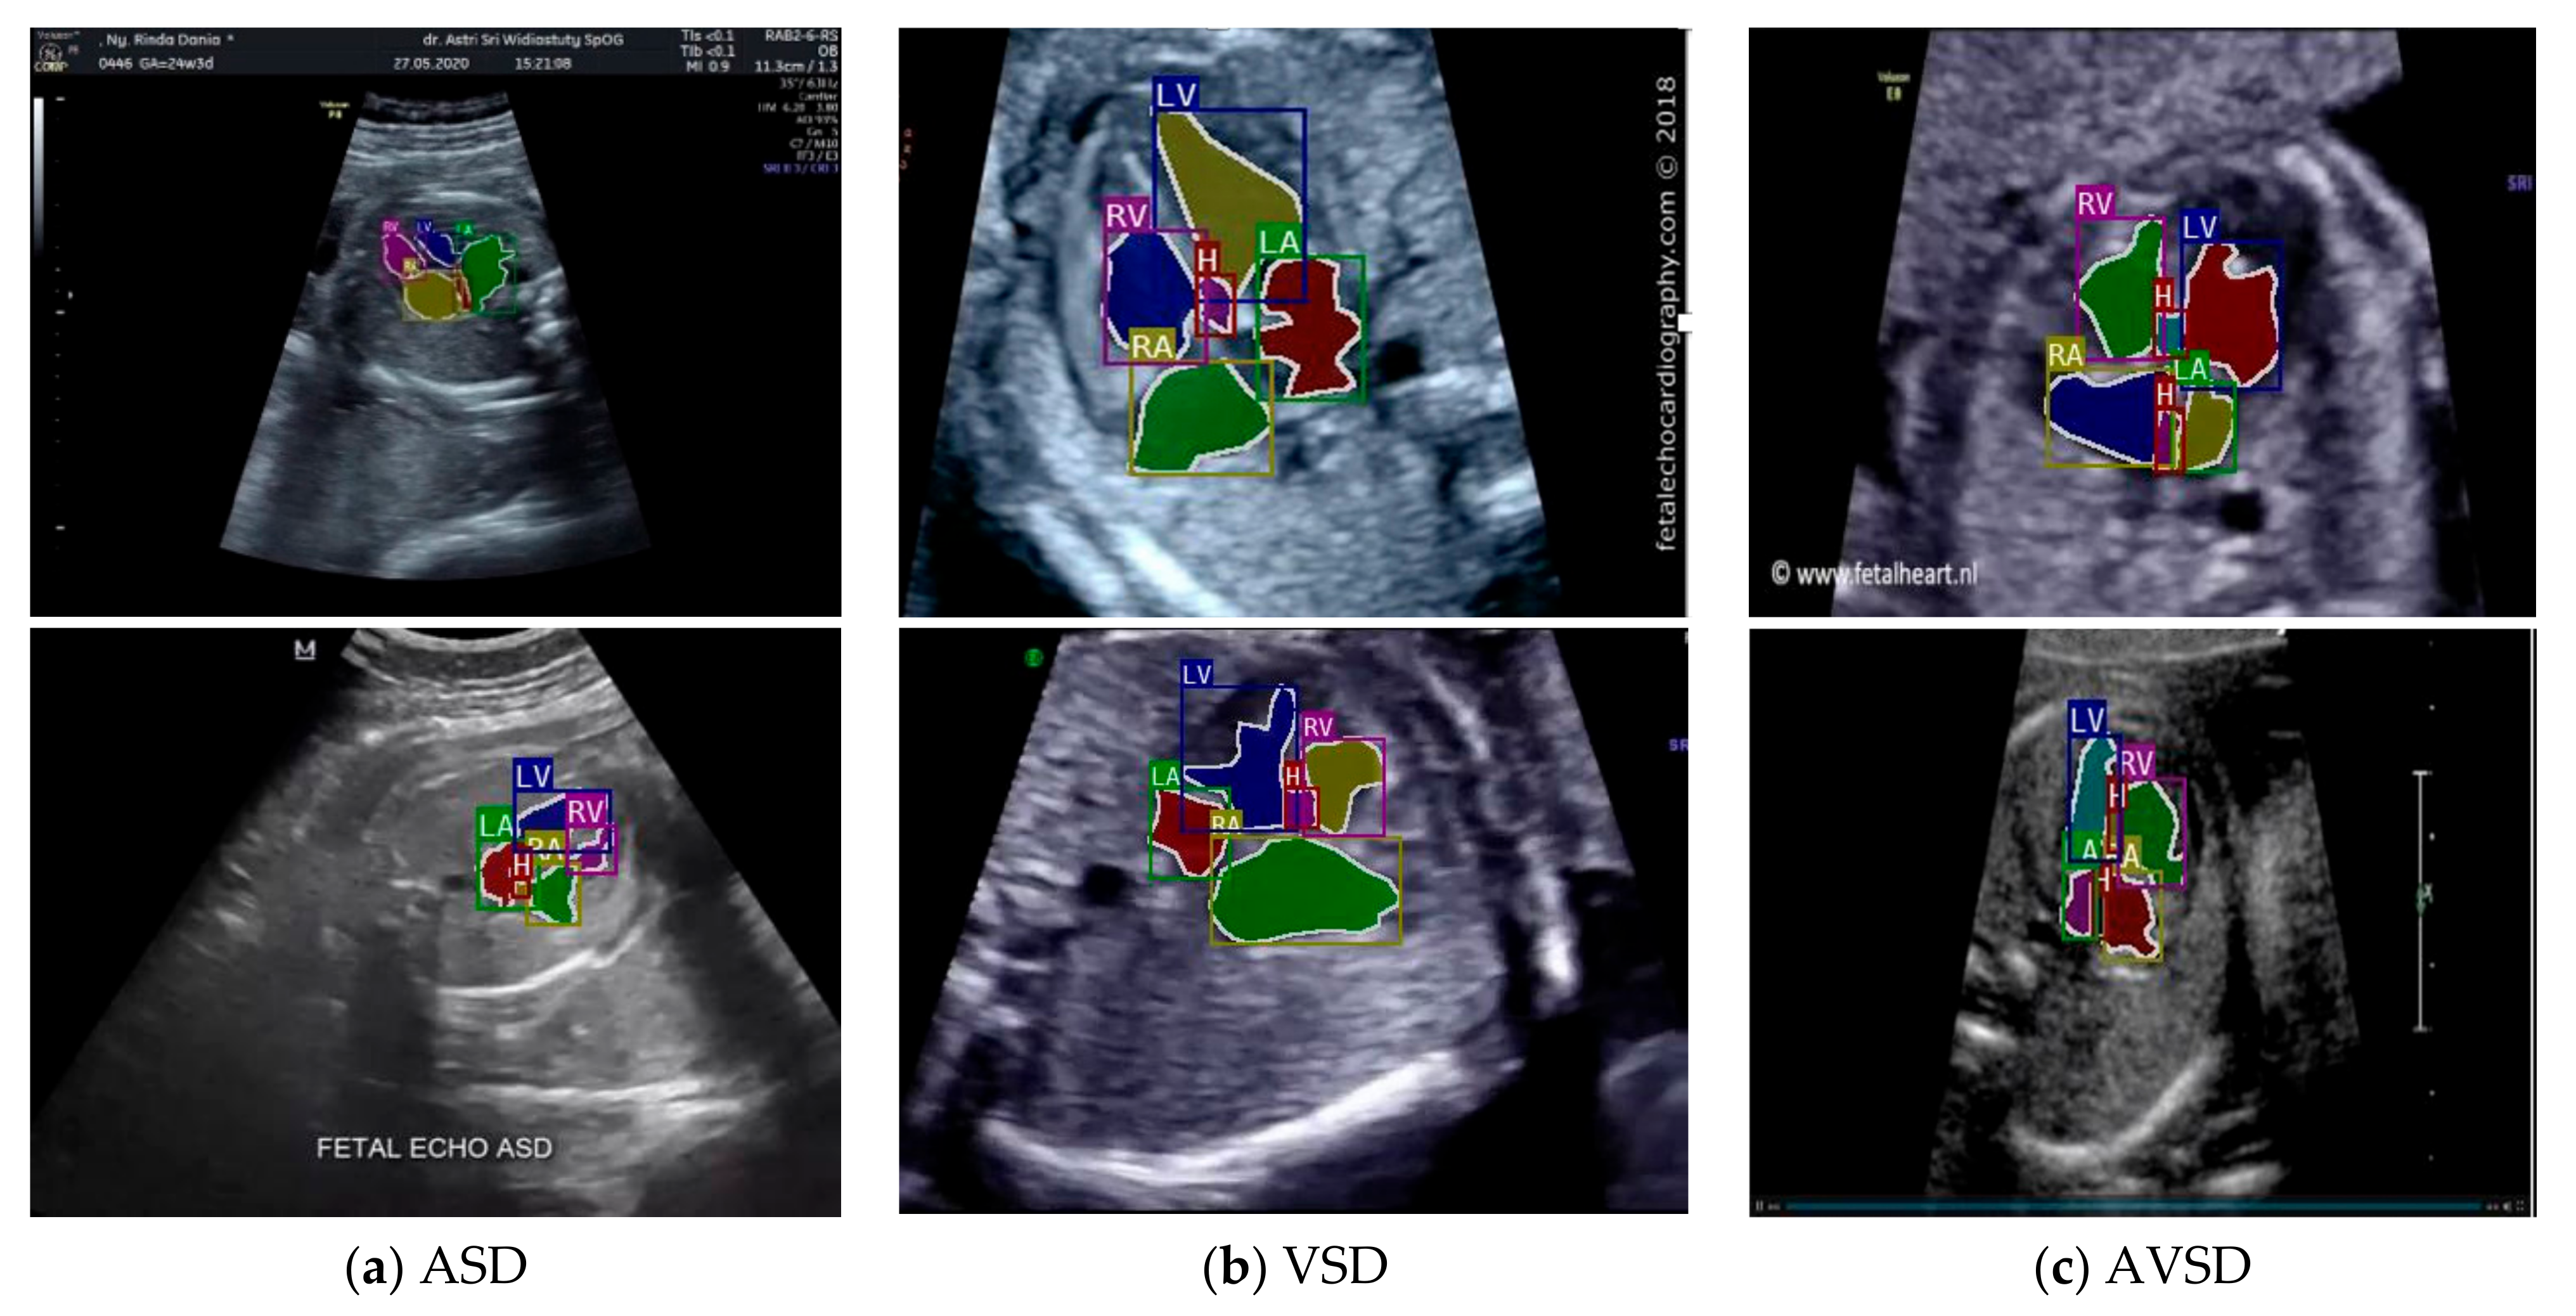

Images with inappropriate anatomical planes (cropped or badly captured) and those with calipers were excluded. The dataset composition was clearly imbalanced (some classes were more frequent than others), as is usually the case in real clinical scenarios. The sample of the raw ultrasound image was based on four views in normal anatomy, as depicted in Figure 2. In such sample, there are the left atrium (LA), left ventricle (LV), right atrium (RA), right ventricle (RV), ductus arteriosus (DUCT), superior vena cava (SVC), aorta ascendens (AoA), aorta descendens (Ao), and main pulmonary artery (MPA), whereas the sample of the raw ultrasound image of abnormal anatomy structure, with the three heart defects such as ASD, VSD, and AVSD condition, is compared to normal anatomy structure in Figure 3. In the abnormal structure, there are hole (H) as heart defect in each condition. Each defect has the variation of hole size; such hole size indicates the disease severity. However, in this study, we only detected the hole, without measuring the hole size.

Figure 3.

Fetal heart scan in 4CH view for CHDs detection: (a) ASD; (b) VSD; (c) AVSD; and (d) Normal.

Especially for heart defect detection, only 4CH view was used to analyze ASD, VSD, and AVSD images. Annotated images indicate the position of defect in the atrium, ventricle, or both of them. Figure 4 depicts the sample of annotated images for a standard view of 4CH, 3VT, LVOT, and RVOT, and Figure 5 shows the sample annotated images of defect position in ASD, VSD, and AVSD. Finally, the whole annotated images are labelled as the ground truth database, and it was saved in the JSON file format (json).

Figure 5.

The sample of annotated image by maternal–fetal clinician for heart defect detection in case: (a) ASD; (b) VSD; and (c) AVSD. In the annotation, the green line is RA, the red line is LA, the purple line is RV, the blue line is LV, and the yellow line is defect.